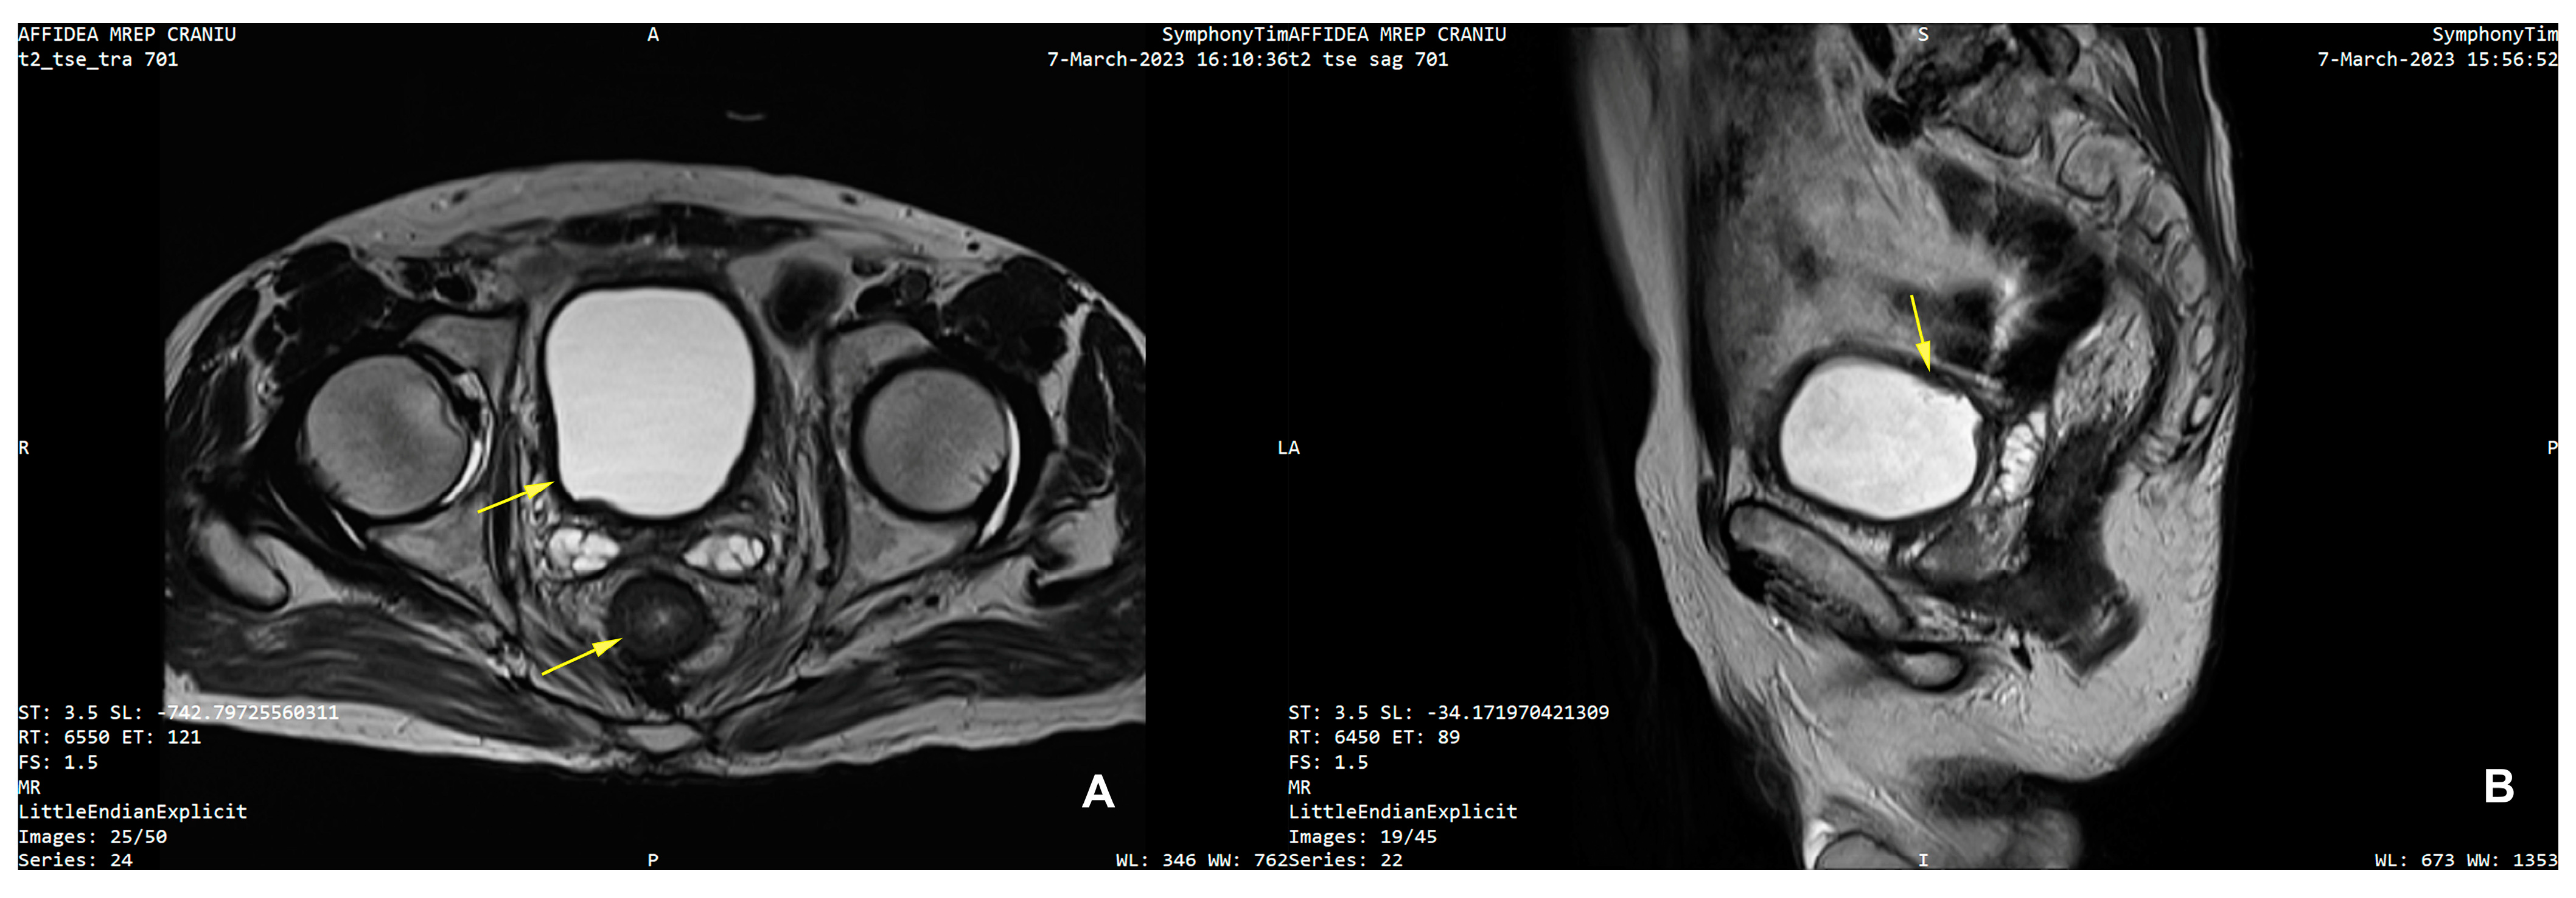

| 25 | Present Case (2025) | 64/M | UCC G3/conventional and signet ring cell | GATA3, CK 20/CK5/6, P63, CDX | colonoscopy, rectal EUS TCB | rectal tenesmus, transit disorders (constipation/small volume diarrhea), moderate dysuria | DISTAL MEDIUM R |

| 25. | Present Case (2025) | 64/M | 0 | NO | Colostomy, NEOADJ CHT GC, RT | 15 M/D | T2N0M0 |